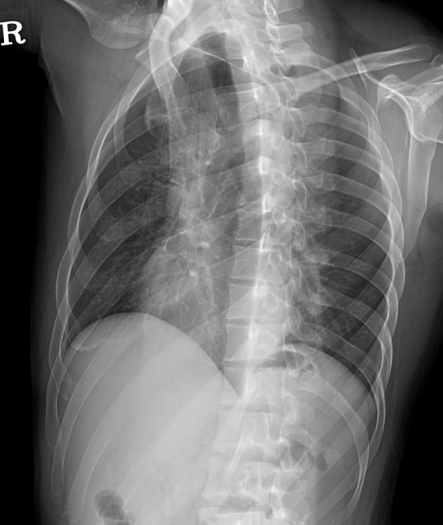

안녕하세요, 오늘은 갈비뼈(늑골, Rib) 촬영방법 중 하나인 Rib AP/PA both oblique(RAO, LAO,RPO,LPO) 촬영법에 대해서 설명하겠습니다. 갈비뼈의 병리학적 상태 혹은 외상에 의한 골절이나 손상을 전체적으로 확인하는데 유용한 검사입니다. 특히 각 자세마다 관찰하고자 하는 부분이 다 다른데요, 그럼 이미지와 함께 설명을 시작하겠습니다.

- LAO : 우측 전방 늑골 관찰 용이

- RAO : 좌측 전방 늑골 관찰 용이

- LPO : 좌측 후방 늑골 관찰 용이

- RPO : 우측 후방 늑골 관찰 용이

Rib Oblique (RAO, LAO)

- 서서 촬영한다

- MSP(정중시상면)과 카세트의 각도가 45도가 되도록 몸을 회전시킨다.

- 턱을 올려 위 늑골과 하악골의 겹침을 방지한다.

- 검사측 팔을 들어올린다

- 위 늑골 : Full inspiration(완전 흡기) 후 촬영

- 아래 늑골 : Full expiration(완전 호기) 후 촬영 -> 횡경막이 올라가고 복부 두께를 줄여 영상의 질을 높일 수 있다.